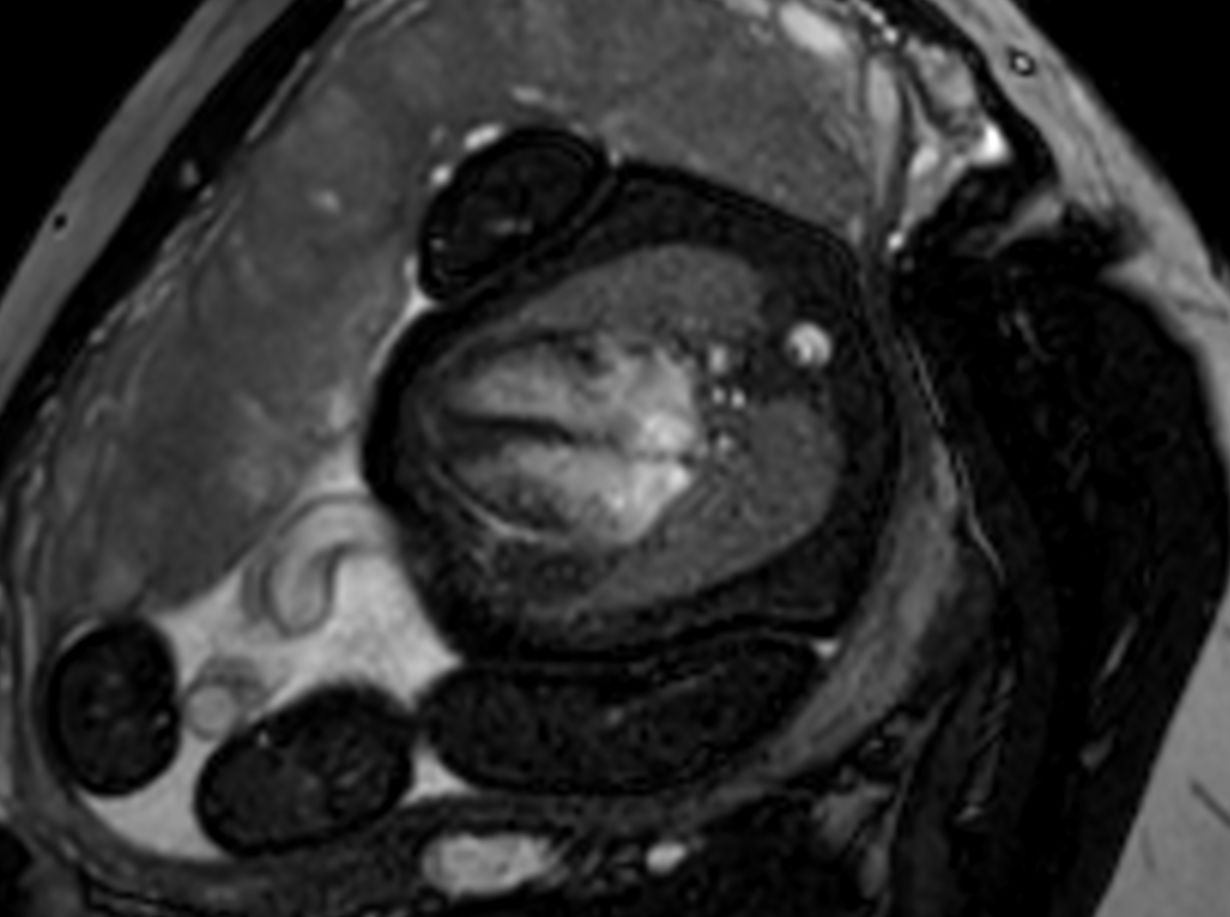

Morphology - bFFE short axis

Morphology - bFFE vertical long axis

Morphology - bFFE 4 chamber